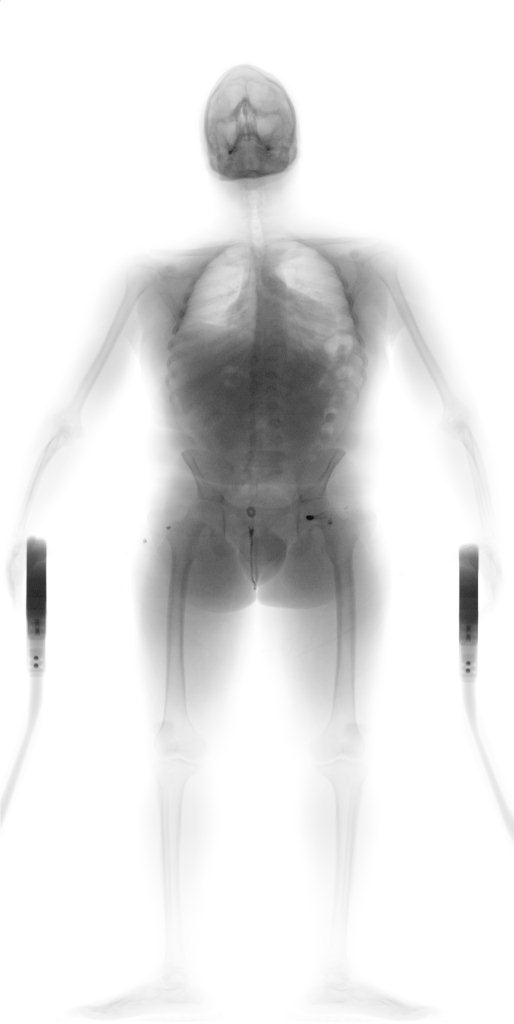

Billede 1: Scanningsbillede fra Københavns lufthavn. Tolderne har udtaget personen til kontrol, og scanningsbilledet afslørede 70 kugler i tarmsystemet med i alt 700 gram kokain.

Billede 5: Demonstrationsbillede af en person med kokain i tarmsystemet.